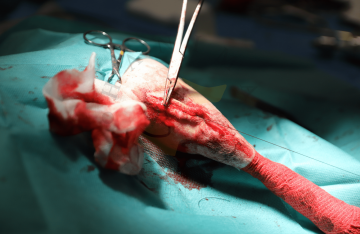

Trochleoplastika

Transpozice tuberositas tibiae

Náhrada předního zkříženého vazu

Amputace